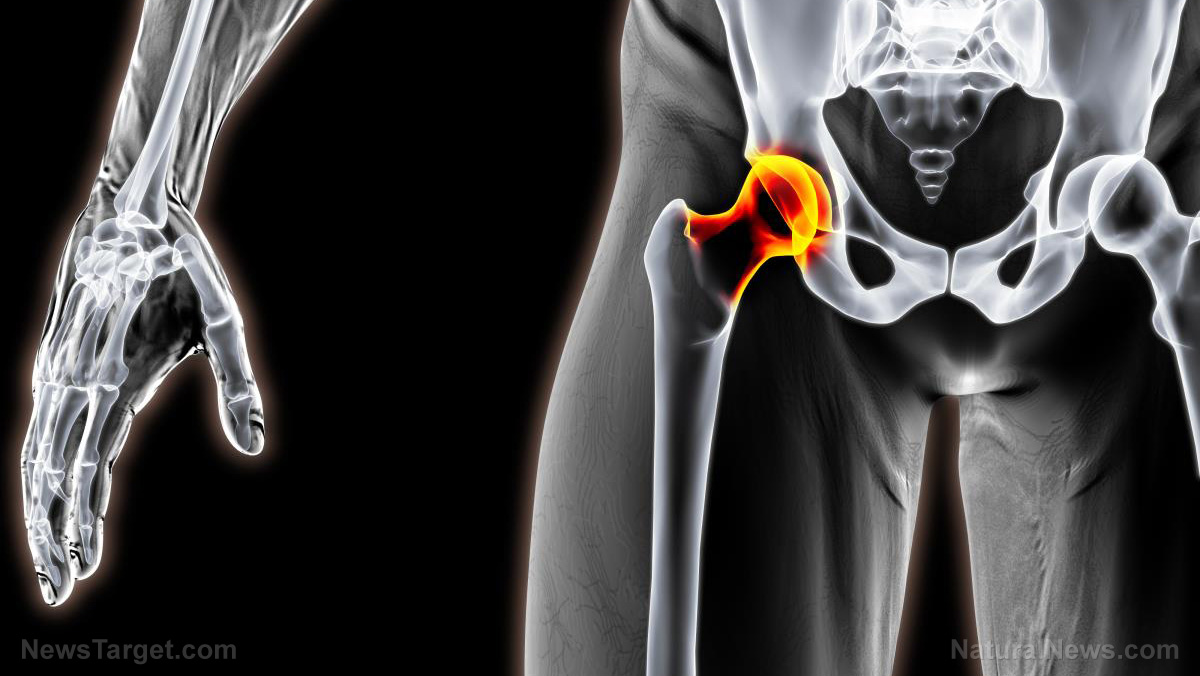

Radiation treatment is likewise used by doctors for dealing with the malignant bone pain. The size of the tumors https://www.Saludaio.com can be decreased by the treatment. Their development can also be managed. This will assist in alleviating the discomfort.

The movements will be affected considerably if the growth of the tumor is near the joints. This is considered to be one of the most typical signs of main Encuentra más cancer. Sometimes, pressure symptoms may also be experienced. The tumors will grow in size and will trigger numerous kinds of pressure signs. For instance, the growths will stand out of the joints. It will trigger permanent damage to it and will be pushed down if the organ is near the tumor.